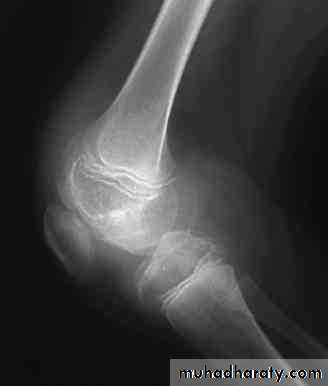

Although bleeding may occur in any area of the body, the hallmark of hemophilia is the hemarthrosis. Bleeding into joints may be induced by minor trauma; nonetheless, many hemarthroses are spontaneous.

Complications• Chronic joint destruction: